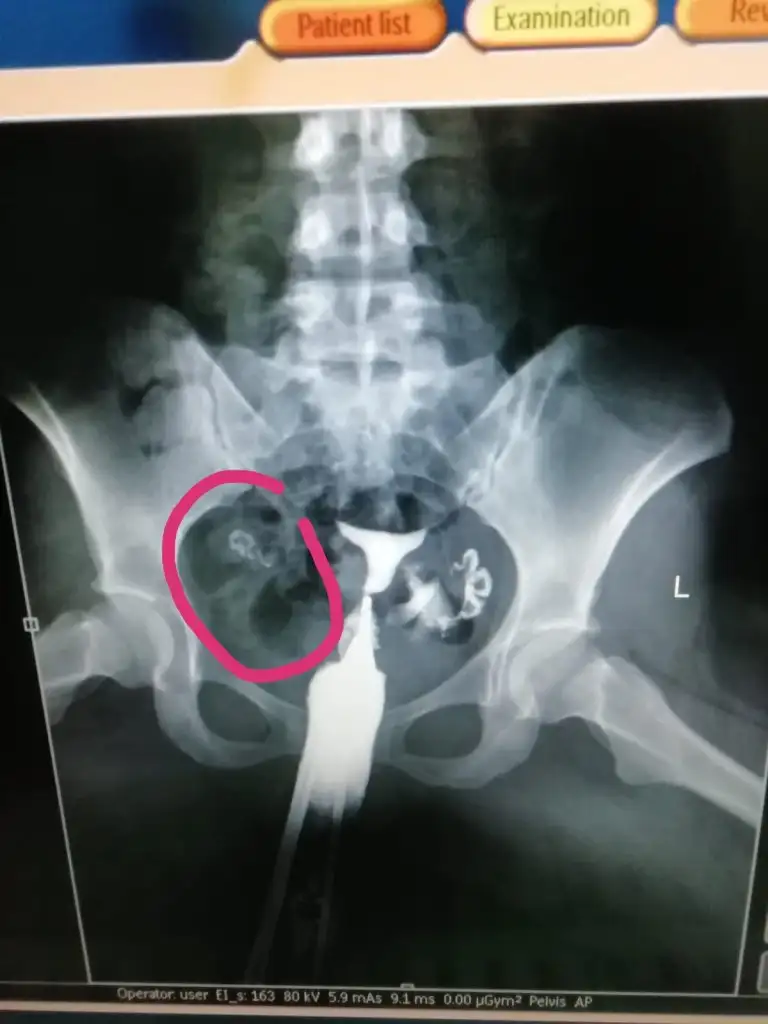

Canım aynen pembe görüntüde geçiş var gerçekten. Zaten benim doktorum bile açık normal ama radyologun raporunu bekleyelim o önemli demişti . Seninki ikinci durumda gayet normal gözüküyor? Dur bakalım radyolog raporu ne zaman yazacak? Bence sorduğunuz kişi daha uzman bu konuda belki de tıkanıklık açıldı şu an gayet normal hadi inşallahFilmden anlayan varsa bakabilir mi? Bi radyologa sorduk sol normal tüp görüntüsü o boğum boğum olan dedi, sağda da tıkanıklık varmış ama görünüyor opak madde geçmiş dedi. Bi sağlık çalışanına daha sorduk o da opak madde geçmiş yapışıklığı açmış dedi sizce? Turuncu olan az verdiği hali pembe olanlar basınçlı verdiği hali

Kuzu ben anlamam ama görüntü olarak evet geçmiş ama az geçmiş gibiFilmden anlayan varsa bakabilir mi? Bi radyologa sorduk sol normal tüp görüntüsü o boğum boğum olan dedi, sağda da tıkanıklık varmış ama görünüyor opak madde geçmiş dedi. Bi sağlık çalışanına daha sorduk o da opak madde geçmiş yapışıklığı açmış dedi sizce? Turuncu olan az verdiği hali pembe olanlar basınçlı verdiği hali